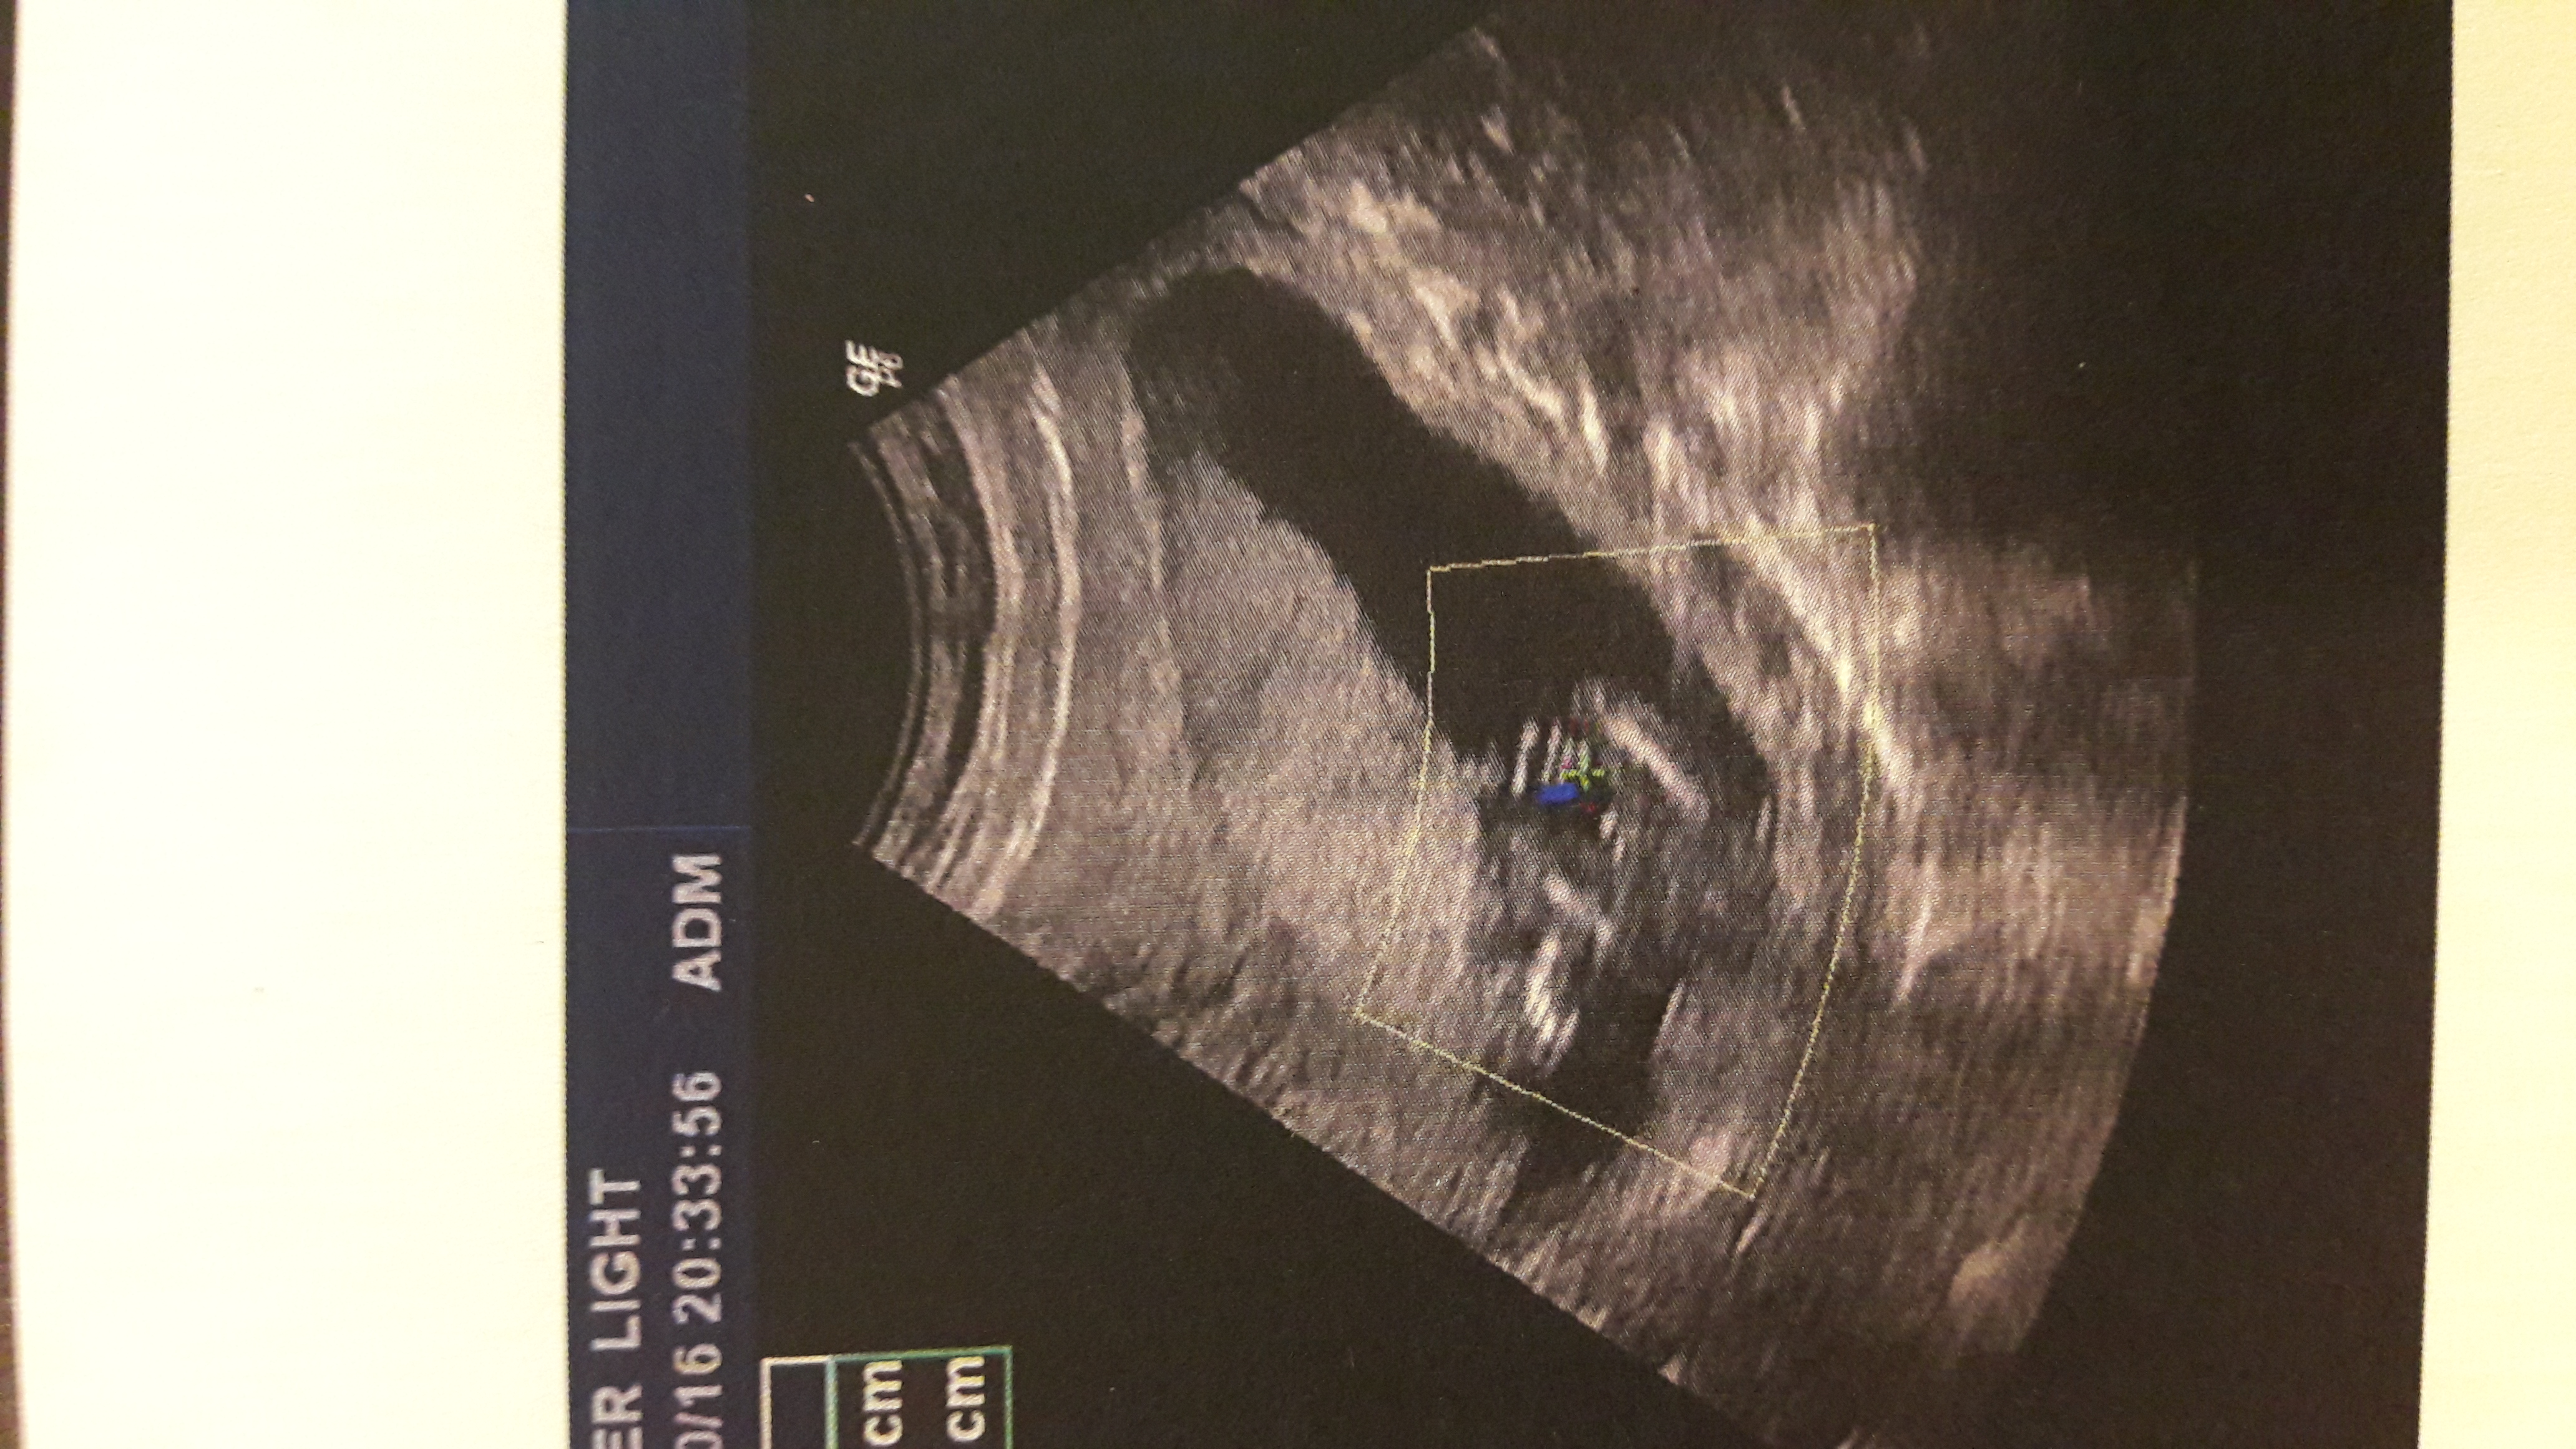

Hi ladies! Today I came to my doctor and during the scan he said that of his point of view it's a Girl but it wasn't very visible. ..now it's 16 weeks...this is a pic! What do you think? Thank you...Attachment 33395

I'm not seeing anything that screams girl?!